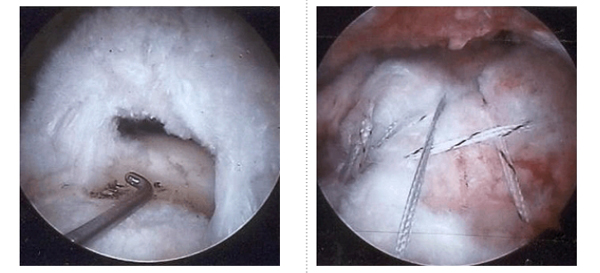

- Surgical: Arthroendoscopy (Acromioplasty, Myorrhaphy)

Rotator Cuff Tear